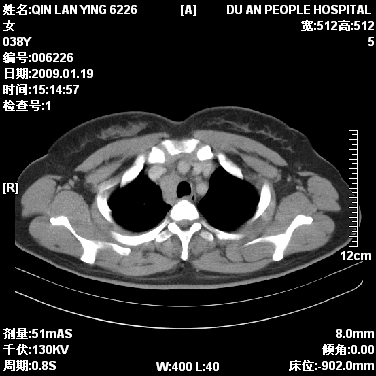

女,38岁,胸疼1个月。wbc:1万4

1)右肺中央型肺癌并右肺上叶阻塞性肺炎、节段性肺不张,纵隔淋巴结转移、右侧胸膜转移、肝脏转移。2)右侧胸腔少量积液。

1、右侧中央型肺癌并阻塞性肺不张,纵隔内、主动脉弓旁、右肺门淋巴结及肝脏转移可能性大,建议纤支镜进一步检查。

2、右侧胸腔积液。

本病例有几个容易诊断的地方:1、右肺上叶前段支气管闭塞,肺不张。2、淋巴结明显肿大。3、肝脏多个类圆形低密度影呈“牛眼征”改变,高度提示转移。

从影像学角度分析      右肺上叶中央型肺癌,并阻塞性不张、肺炎,纵隔淋巴结、膈顶淋巴结转移。

肝内两个大小不等低密度结节,内可见更低密度影,首先考虑肝内转移瘤,但联想到患者wbc1万4,建议楼主还是做个增强比较明确,除外肝脓肿的可能。